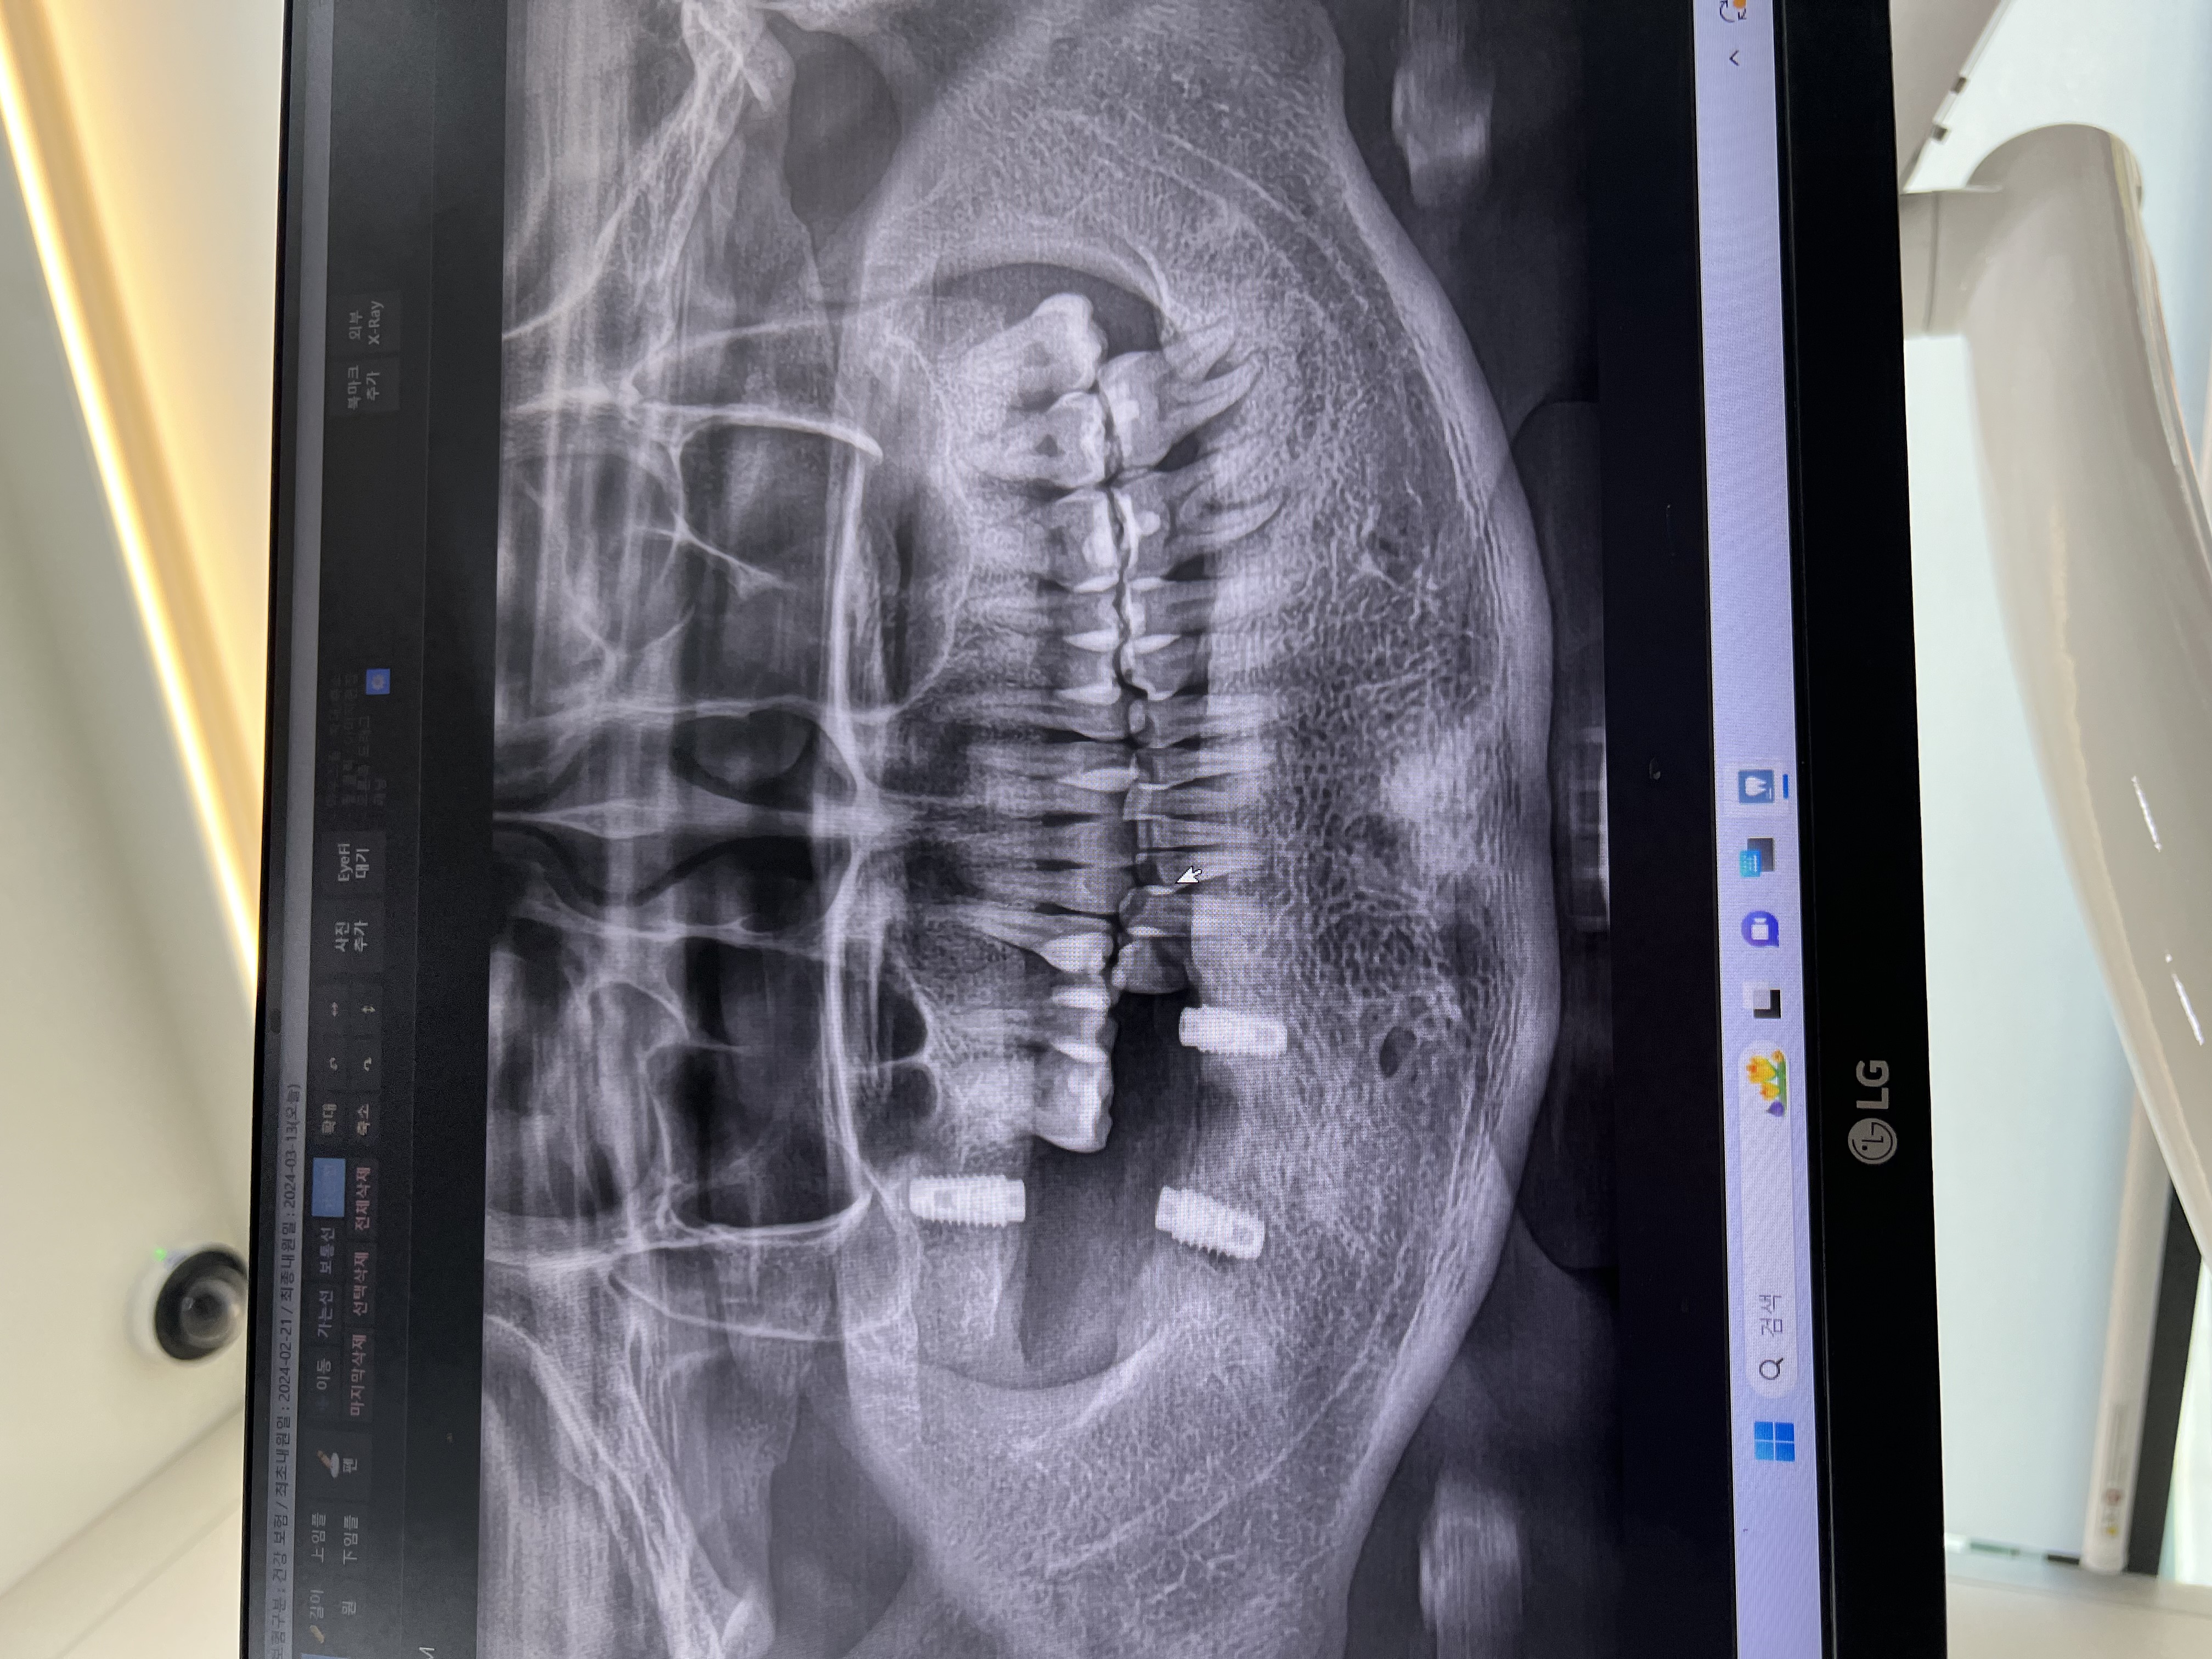

예전에 치료했던 치아가 다시 시리고 불편해서 치과갔어요 치아가 이미 손상이 좀 진행된 상태라 크라운 씌우는 치료가 필요하다 했어요ㅠ 그래도 친절하게 신경치료 여부나 크라운 종류랑 여러 주의사항 알려주셔서 감사했어요. 치료할 때도 섬세하게 괜찮은지 계속 확인해주셧고 생각보다 통증도 크지 않았어요. 임시 크라운을 거쳐서 최종 크라운을 씌웠는데, 모양이나 색도 자연스럽게 맞춰줘서 이질감이 거의 없었어요. 씹을 때 불편했던 부분도 사라지고 훨씬 안정된 느낌이 들었어요. 역시 치아는 관리가 더 중요한 것 같아서 앞으로는 더 신경 써야겠어요ㅠㅠ